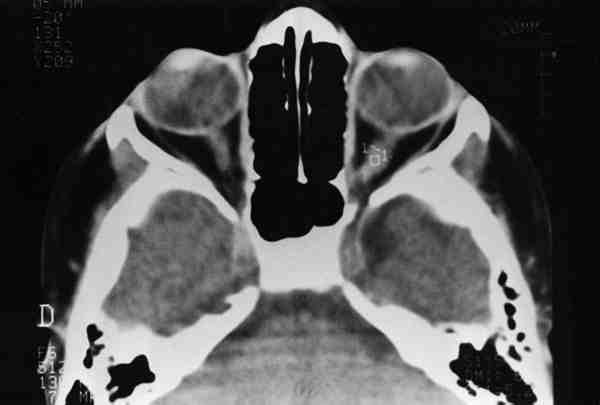

Figura 7

TAC DE ÓRBITA DONDE SE APRECIA GLIOMA DE NERVIO ÓPTICO IZQUIERDO (AÑO 1985). SE OBSERVA EL ASPECTO FUSIFORME Y SIMÉTRICO DE LA LESIÓN.